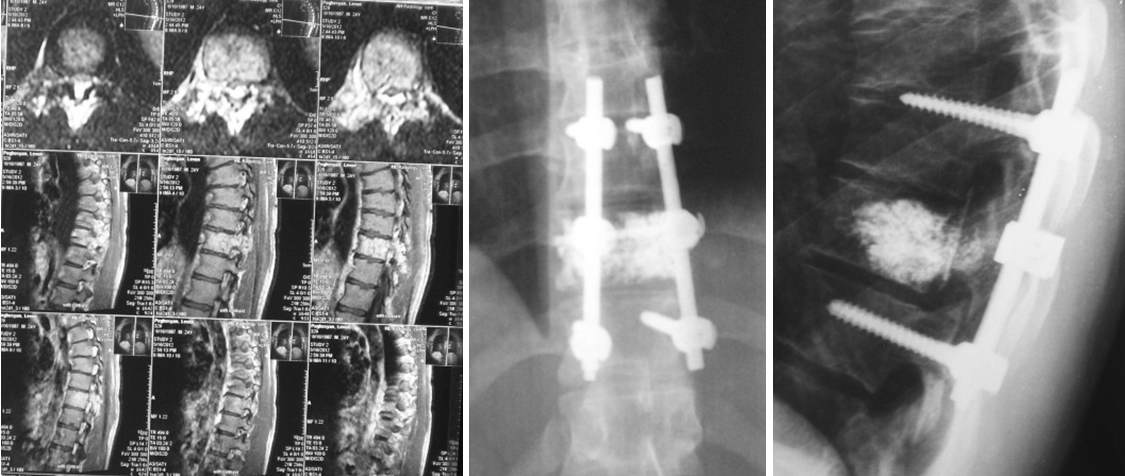

Стеноз позвоночного канала и нестабильность позвонков поясничного отдела позвоночника |

До оперативной коррекции После оперативной коррекции

Во время стеноза (сужения) позвоночного канала, для освобождения спинного мозга, удаляются задние элементы позвонков, и, как во время их неустойчивости, производится транспедикулярная фиксация позвоночника.